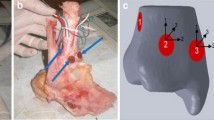

After the foot skeleton and contour were built, all ligaments were connected with lines in the physiological position, and a complete foot model was generated. According to the anatomical data of the joint surface, cartilage boundaries were established, and cartilage joints were built with Geomagic with an offset thickness of 1 mm. Only the fibula and tibia of the calcaneal talus and the related cartilages and ligaments were required to be retained per the analysis requirements. Thus, a relatively complete 3D finite element model of the ankle joint of the normal adults was built. Based on the cartilage of the normal model, the talus cartilage was divided into nine regions using the nine-grid partition method. Studies have shown that area 4 is the most common area for talus cartilage injuries [17, 18]. This study simulated defects in cartilage and subchondral bones in region 4 of the talus. Because the existing literature did not study the area size of finite element and talus injury, we selected the following FEA: the experimental measurement depth 1 mm with the area defect sizes being 2 mm * 2 mm, 4 mm * 4 mm, 6 mm * 6 mm, 8 mm *8 mm, 10 mm *10 mm, and 12 mm * 12 mm (Fig. 2).

Therefore, our group used the three-dimensional finite element mechanics of different OLT defects to simulate the changes in the stress and displacement of the ankle joint in the heel-strike phase, the midstance, and the push-off phase. We found that compared to normal talus cartilage when the area defect was less than 6 mm*6 mm, the equivalent stresses of the proximal talus, tibial cartilage, and talus cartilage (Fig. 5) did not change significantly compared to those of the normal talus cartilage. However, when the area size was greater than 6 mm*6 mm, stress increased with increasing area sizes of the defect in the midstance and push-off phases. The maximum stress could be increased more than 2–3 times but had little impact on the heel-strike phase. According to the motion mechanics of the ankle joint and the gait cycle, the heel-strike phase is when the heel touches the ground, which is the beginning of the support phase [32]. At this time, the front articular surface of the talus (area 1/2/3, Fig. 3) was in contact with the tibia, and the defect area was in zone 4 (Fig. 3), which was located in the middle medial part of the talus, and the stress was small. Therefore, the stress change was not evident in the heel-strike phase. In contrast, the stress in talus zone 4 increased and reached the maximum value in the midstance and push-off phases. The talus position is different during the movement of the ankle joint. We believe that this is why biological stresses have different tendencies.